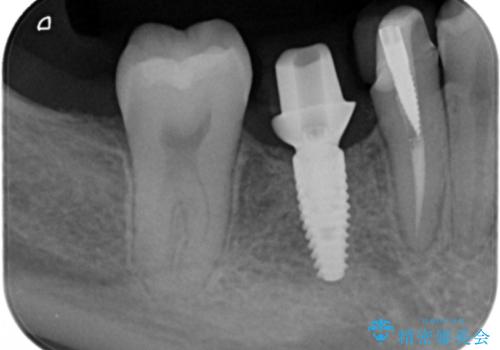

奥歯のインプラント

- 右下6番が保存不可能だったため、やむなく抜歯しました。

インプラント治療をご希望されたため、植立を行いました。

インプラントを入れる際、部分的に骨を増やす処置を行っています。